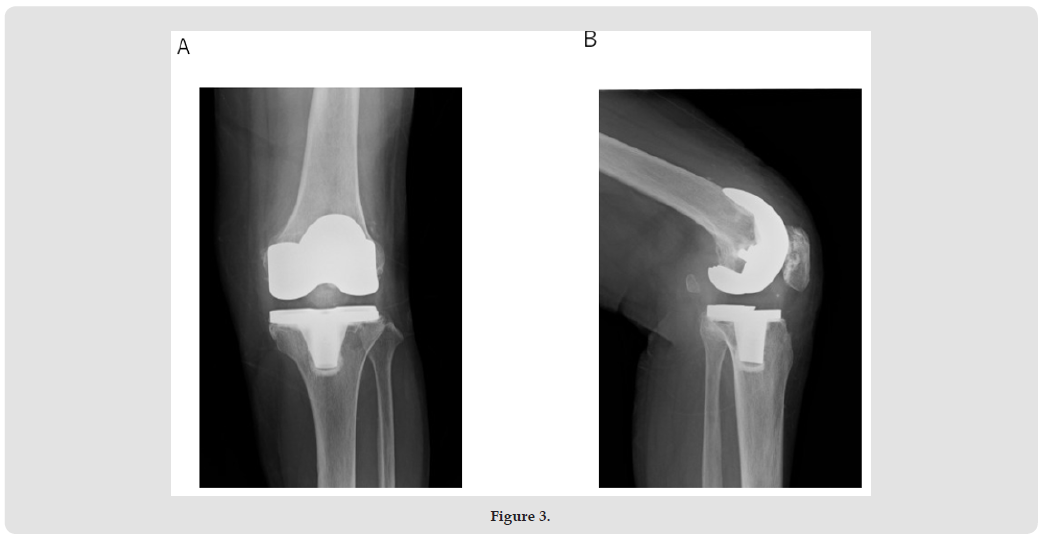

A 77-year-old woman with osteoarthritis in her left knee underwent Zimmer Persona posterior stabilizer type TKA in another hospital about 3.5 years ago. Three years later, she experienced severe pain and a locking sensation in her left knee while shopping. A swelling and tenderness were observed in the left knee. A joint puncture was then performed. The aspirated fluid resembled blood. The bacterial culture was negative. Subsequently, severe pain and a locking sensation in the knee appeared occasionally. Therefore, she was referred to our department for surgery. Her history was unremarkable. A physical examination revealed swelling and slight local heat of the left knee. Anterior instability was not observed, but varus and valgus instability were eminent. The range of motion (ROM) was 0 to 123o. The knee-rating scale of the Hospital for Special Surgery (HSS) was 53. Radiographs showed that the tibiofemoral joint was not dislocated, and loosening of the implants was not found (Figures 1A & 1B). In the stress radiographs, varus and valgus instabilities (ext. 0o, flex. 30o) were noted (Figures 2A-2D).